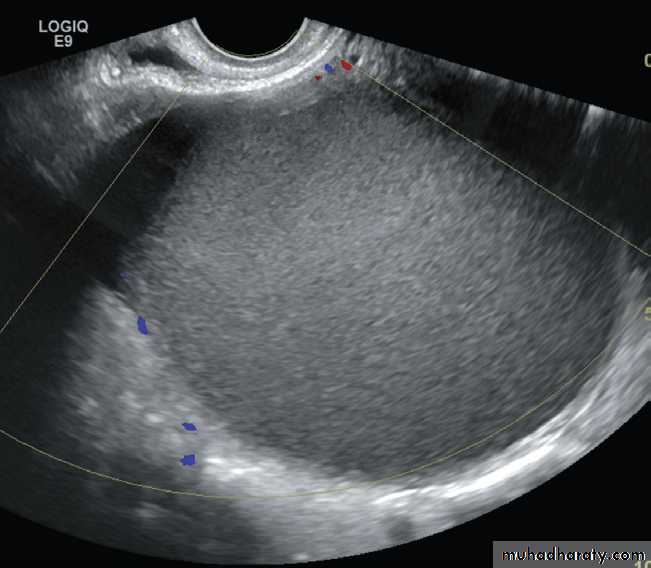

At ultrasound

Endometriosis is usually seen as a cystic mass with homogeneous internal echogenicity in the adnexal region and/or pouch of Douglas corresponding to the chocolate cysts found on pathological examination .